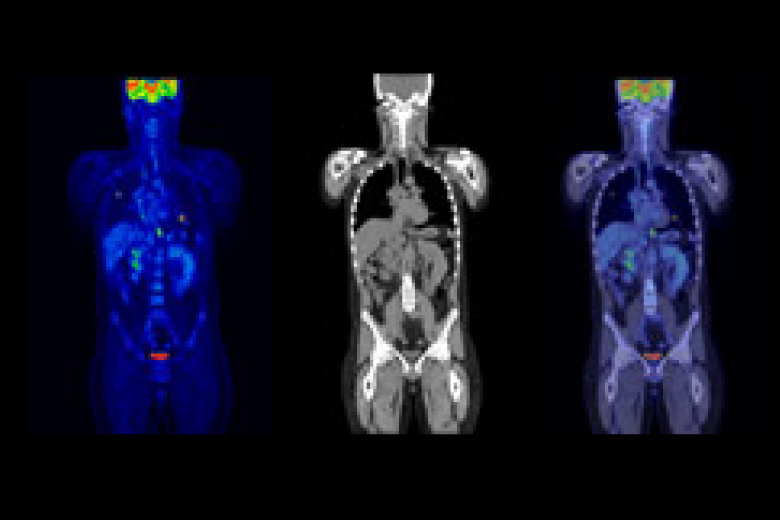

PET検査とは、「陽電子放射断層撮影」という意味で、ポジトロン・エミッション・トモグラフィー(Positron Emission Tomography)の略です。当院の検査装置は、PETとCTを同時に短時間で撮影ができます。PETではがん細胞の活動状況を知ることを得意とし、CTでは臓器の形をしっかりと映し出すことを得意とします。その二つの画像を重ね合わせてみることにより、正確な診断を行うことができます。全身のがん、脳、心臓などの病気の診断に有効です。